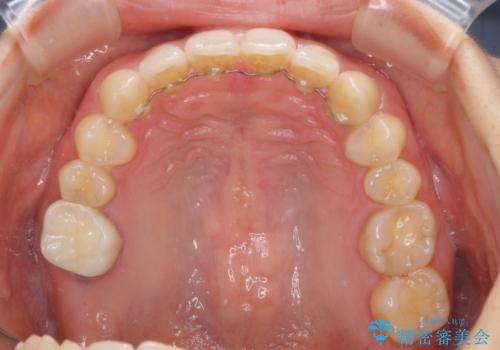

隙間だらけの歯列をきれいに インビザライン矯正とセラミック補綴治療

- 前歯の隙間と奥歯の目立つ銀歯を気にして来院された患者様です。

インビザラインにより下顎前歯の隙間を閉じるとともに、奥歯の咬み合わせを改善させることとしました。

矯正治療後には、銀歯のクラウンをセラミッククラウンへ替える補綴治療を行うこととしました。